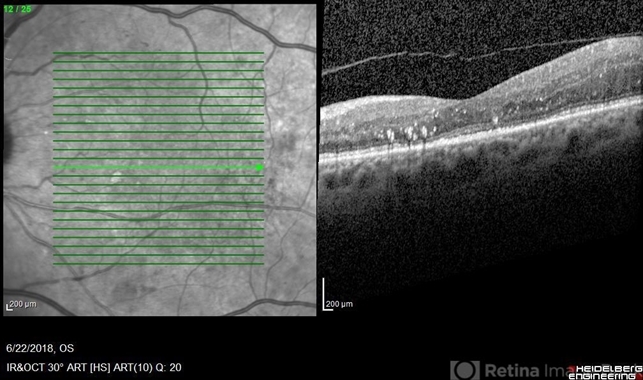

- Diabetic macular edema initial presentation

- diabetic macular edema, anti-VEGF

Optical coherence tomography system

Heidelberg Spectralis - Description

- Decreased cystic changes and resolved subretinal fluid, lipid remains present.